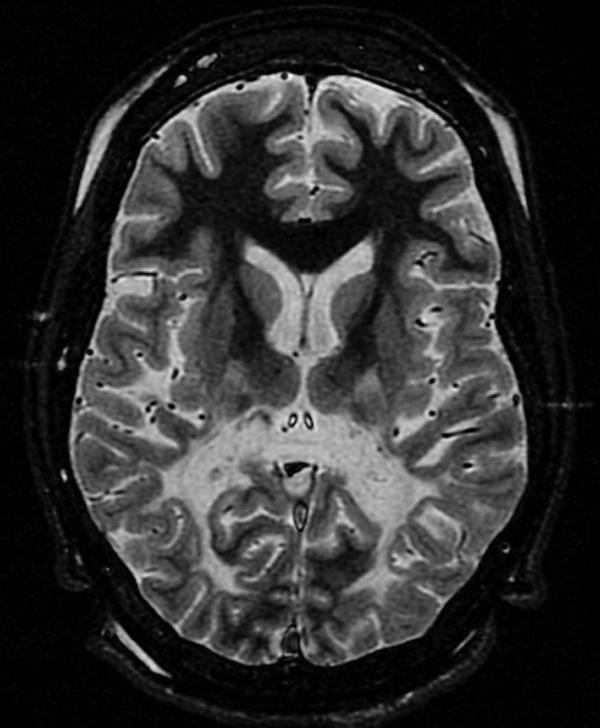

Магнитно-резонансная томография головного мозга: на начальных стадиях заболевания выявляются характерные изменения в белом веществе головного мозга. На томограммах в режиме Т2-взвешенного изображения определяется гиперинтенсивный сигнал в области валика мозолистого тела. На этой стадии контрастное усиление в поражённых участках отсутствует. По мере прогрессирования заболевания наблюдается симметричное поражение затылочных и теменно-затылочных отделов мозга с вовлечением прилежащего субкортикального белого вещества. Развивающийся воспалительный процесс в зонах демиелинизации приводит к нарушению целостности гематоэнцефалического барьера, что проявляется накоплением контрастного вещества при повторных исследованиях[3].